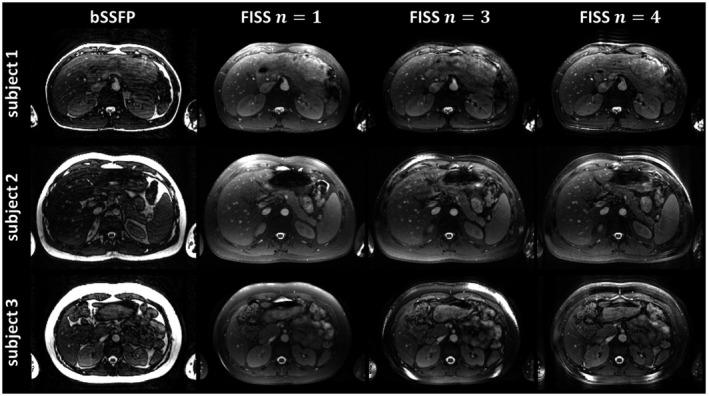

A periodic interruption of the balanced steady-state free precession (bSSFP) readout train (FISS) has been previously proposed for 2D radial imaging. FISS modulates the bSSFP frequency response pattern in terms of shape, width and location of stop band (attenuated transverse magnetization). Depending on the FISS interruption rate, the stop band characteristic can be exploited to suppress the fat spectrum at 3.5 ppm, thus yielding intrinsic fat suppression. For conventional 2D Cartesian sampling, ghosting/aliasing artifacts along phase-encoding direction have been reported. In this work, we propose to extend FISS to 3D Cartesian imaging and report countermeasures for the previously observed ghosting/aliasing artifacts. Key parameters (dummy prepulses, spatial resolution, and interruption rate) are investigated to optimize fat suppression and image quality. FISS behavior is examined using extended phase graph simulations to recommend parametrizations which are validated in phantom and in vivo measurements on a 1.5T MRI scanner for 3 applications: upper thigh angiography, abdominal imaging, and free-running 5D CINE.

Using optimized parameters, 3D Cartesian FISS provides homogeneous and consistent fat suppression for all 3 applications. In upper thigh angiography, vessel structures can be recovered in FISS that are obscured in bSSFP. Fat suppression in free-running cardiac CINE resulted in less fat-related motion aliasing and yielded better image quality.